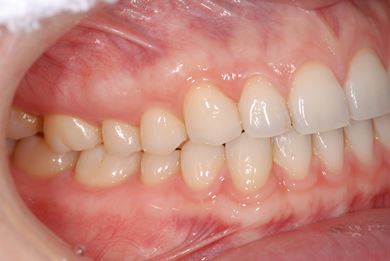

| 性別/年齢 | 女性 / 29歳 | ||||||||||||||||||||||||||||||||

| 主訴 | インプラント治療と、親知らずの抜歯の相談。なるべく安価で、短期間で終了して欲しい。 | ||||||||||||||||||||||||||||||||

| 治療方針 | 欠損部分をインプラント治療にて、機能的・審美的回復を行う。 | ||||||||||||||||||||||||||||||||

| 治療内容 | インプラント1本、メタルボンドセラミッククラウン1本 | ||||||||||||||||||||||||||||||||

| 総治療費 | 252,000円 | ||||||||||||||||||||||||||||||||

| 治療期間 | 11ヶ月 |